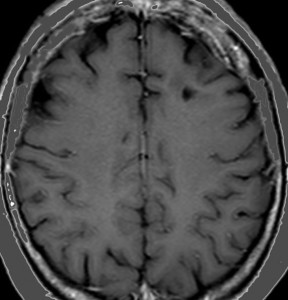

乳癌の多発脳転移の例

全脳照射3ヶ月後のMRIです。左の頭頂葉の転移巣は消失していますし,左の小脳転移は手術摘出できていて再発もありません。このように乳癌は,多発転移であっても比較的に制御しやすいものです。しかし,一度消えた病巣が再発したり,また新たなところに脳転移が生じるという可能性もあります。